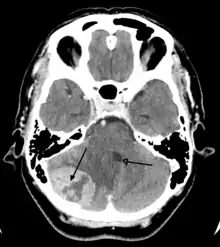

Imaging

Medical imaging plays a central role in the diagnosis of brain tumors. Early imaging methods – invasive and sometimes dangerous – such as pneumoencephalography and cerebral angiography have been abandoned in favor of non-invasive, high-resolution techniques, especially magnetic resonance imaging (MRI) and computed tomography (CT) scans,[37] though MRI is typically the reference standard used.[39] Neoplasms will often show as differently colored masses (also referred to as processes) in CT or MRI results.

- Benign brain tumors often show up as hypodense (darker than brain tissue) mass lesions on CT scans. On MRI, they appear either hypodense or isointense (same intensity as brain tissue) on T1-weighted scans, or hyperintense (brighter than brain tissue) on T2-weighted MRI, although the appearance is variable.

- Contrast agent uptake, sometimes in characteristic patterns, can be demonstrated on either CT or MRI scans in most malignant primary and metastatic brain tumors.

- Pressure areas where the brain tissue has been compressed by a tumor also appear hyperintense on T2-weighted scans and might indicate the presence a diffuse neoplasm due to an unclear outline. Swelling around the tumor known as peritumoral edema can also show a similar result.